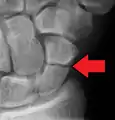

A more obvious scaphoid fracture on a scaphoid view X ray

Scaphoid fractures are often diagnosed using plain radiographs and multiple views are obtained as standard.[9] However, not all fractures are apparent initially.[7] In 1/4 of cases, the clinical examination suggests a fracture, but the X-ray does not show it, even though there is indeed a fracture.[10] Therefore, people with tenderness over the scaphoid (those who exhibit pain to pressure in the anatomic snuff box ) are often splinted in a thumb spica for 7–10 days at which point a second set of X-rays is taken.[7] If a minimally displaced fracture was present initially, healing will now be apparent. Even then a fracture may not be apparent. A CT Scan can then be used to evaluate the scaphoid with greater resolution. The use of MRI, if available, is preferred over CT and can give one an immediate diagnosis.[11] Bone scintigraphy is also an effective method for diagnosis fracture which do not appear on Xray.[12]